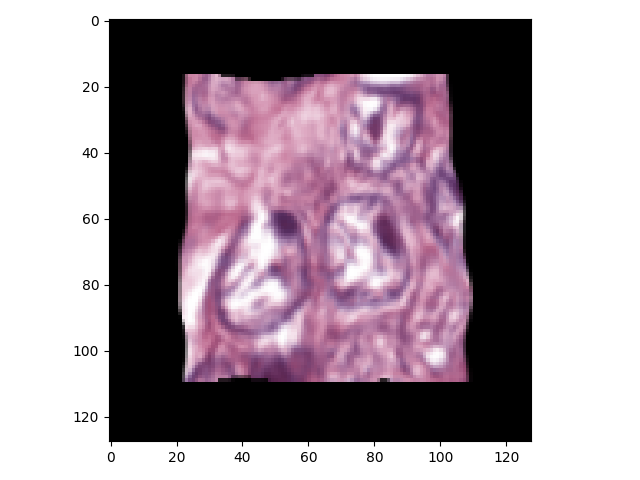

Deep learning models often have millions of parameters so that it needs large-scale sample dataset to avoid the overfitting problem. In fact, the datasets of our nuclei segmentation task often contain only tens of images. Moreover, labeling an 1000*1000 image which contains hundreds of nuclei usually cost a specialist at least 5 hours. Hence it is impossible to manually label sufficient and nuclei boundaries accurately for training deep learning models. Data augmentation is an essential approach to overcome the over-fitting problem caused by lacking samples. The training samples, i.e.the patches, are randomly extracted from the H&E stained images in the training datasets. Five augmentation techniques are used together in our experiments including random elastic transformation, rescale, affine transformation, shift, flip and rotate. Each training sample(one patch extracted from a whole image) as well as the corresponding target are processed by the data augmentation procedure. Given a training sample, which is a RGB image with its corresponding ground truth , we transform to and to . and are the real input and target of the neural network. The rescaling factors are set as a random number between 0.5-1.5. We employ Simard’s method[32] to do elastic transforming. Two hyper-parameters and need to be manually set to control how dramatic the original image is transformed. In our experiment, is set to a random number between 100-200, is set to 12.

Besides transforming the input sample, it is necessary to do the same transformation on targets to maintain consistency. The one-hot encoding target consists of only binary values. However, the transformed target has some float-point numbers caused by bilinear interpolation we used for elastic transformation. They need to be binarized by the following rules:

Let the value of one pixel is , where , and represents the label for , and respectively.

1. if , , else

2. if and , , else

3. if or , , else

An example of data augmentation is illustrated in Fig.4.